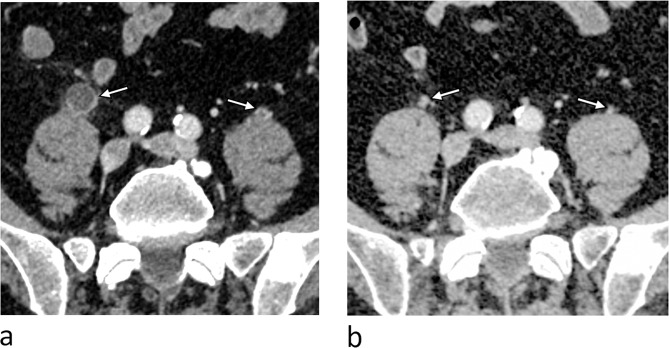

背景:卡巴他赛(cabazitaxel, CBZ)是转移性去势抵抗性前列腺癌(mCRPC)患者主要有效的治疗选择之一。膀胱炎和血尿是与CBZ治疗相关的最显著的非血液学不良事件。但由于cbz引起的输尿管炎的患病率尚未得到深入研究,因此进行了病例系列调查,以强调该疾病的临床相关性和潜在的治疗方案。病例介绍:2014年6月至2024年5月,在Vejle医院肿瘤科诊断为mCRPC的354例患者接受了CBZ治疗。共有36例患者(10%)出现输尿管炎样症状,表现为骨盆、下腹部或侧腹不适,伴或不伴血尿。36例患者中有29例(80%)存在输尿管改变的影像学证据,部分患者伴有肾积水/输尿管积水。在CBZ治疗之前,36例患者中有7例(19%)记录了骨盆或下腹部的放疗。各种镇痛药和剂量调整被考虑用于治疗cbz引起的输尿管炎,治疗停止产生最有利的结果。结论:CBZ治疗过程中发生输尿管炎是临床中被低估的不良反应。血尿和肾积水/输尿管积水是最常见的并发症。止痛剂和减少剂量都应该考虑治疗,而某些个体可能需要停止治疗。

Case presentation: Between June 2014 and May 2024, 354 patients diagnosed with mCRPC were treated with CBZ at the Department of Oncology, Vejle Hospital. A total of 36 patients (10%) exhibited ureteritis-like symptoms, presenting with discomfort in the pelvis, lower abdomen, or flanks, with or without hematuria. Radiological evidence of ureter changes was present in 29 out of 36 individuals (80%), along with hydronephrosis/hydroureter in some patients. Prior to therapy with CBZ, radiation to the pelvis or lower abdomen was documented in 7 out of 36 patients (19%). Various analgesics and dosage modifications were considered for the therapy of CBZ-induced ureteritis, with treatment discontinuation yielding the most favorable results.